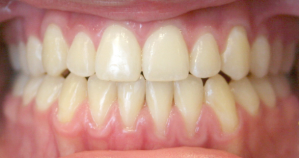

Open Bite

An open bite occurs when there is insufficient vertical overlap of the teeth. It is caused by oral habits such as a tongue thrust, thumb or finger sucking or when the jaws don’t grow evenly. Timing of treatment is critical to the overall success of the therapy.

How can an open bite be orthodontically corrected?

An open bite can be corrected through growth modification of the jaws using braces, extrusion of the anterior teeth and in some cases surgical correction of the jaws. Also breaking oral habits, such as digit sucking, will facilitate the correction of an open bite.

Before and After Photos: Open Bite Correction